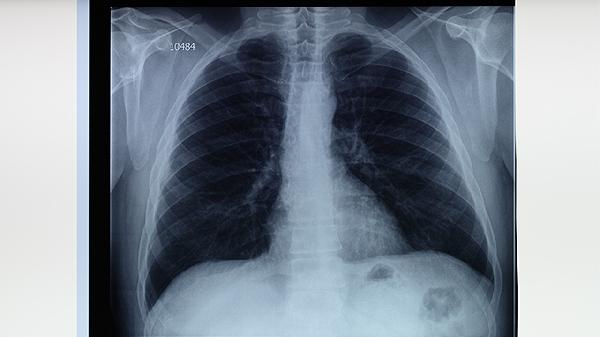

胸部X線(xiàn)可顯示肺結(jié)核的典型病變,如上肺野浸潤(rùn)影、空洞形成等。該檢查能快速評(píng)估肺部病變范圍,但對(duì)早期病變和小病灶敏感性較低。X線(xiàn)表現(xiàn)需結(jié)合臨床癥狀和其他檢查綜合判斷,部分非結(jié)核性疾病也可能出現(xiàn)類(lèi)似影像學(xué)改變。